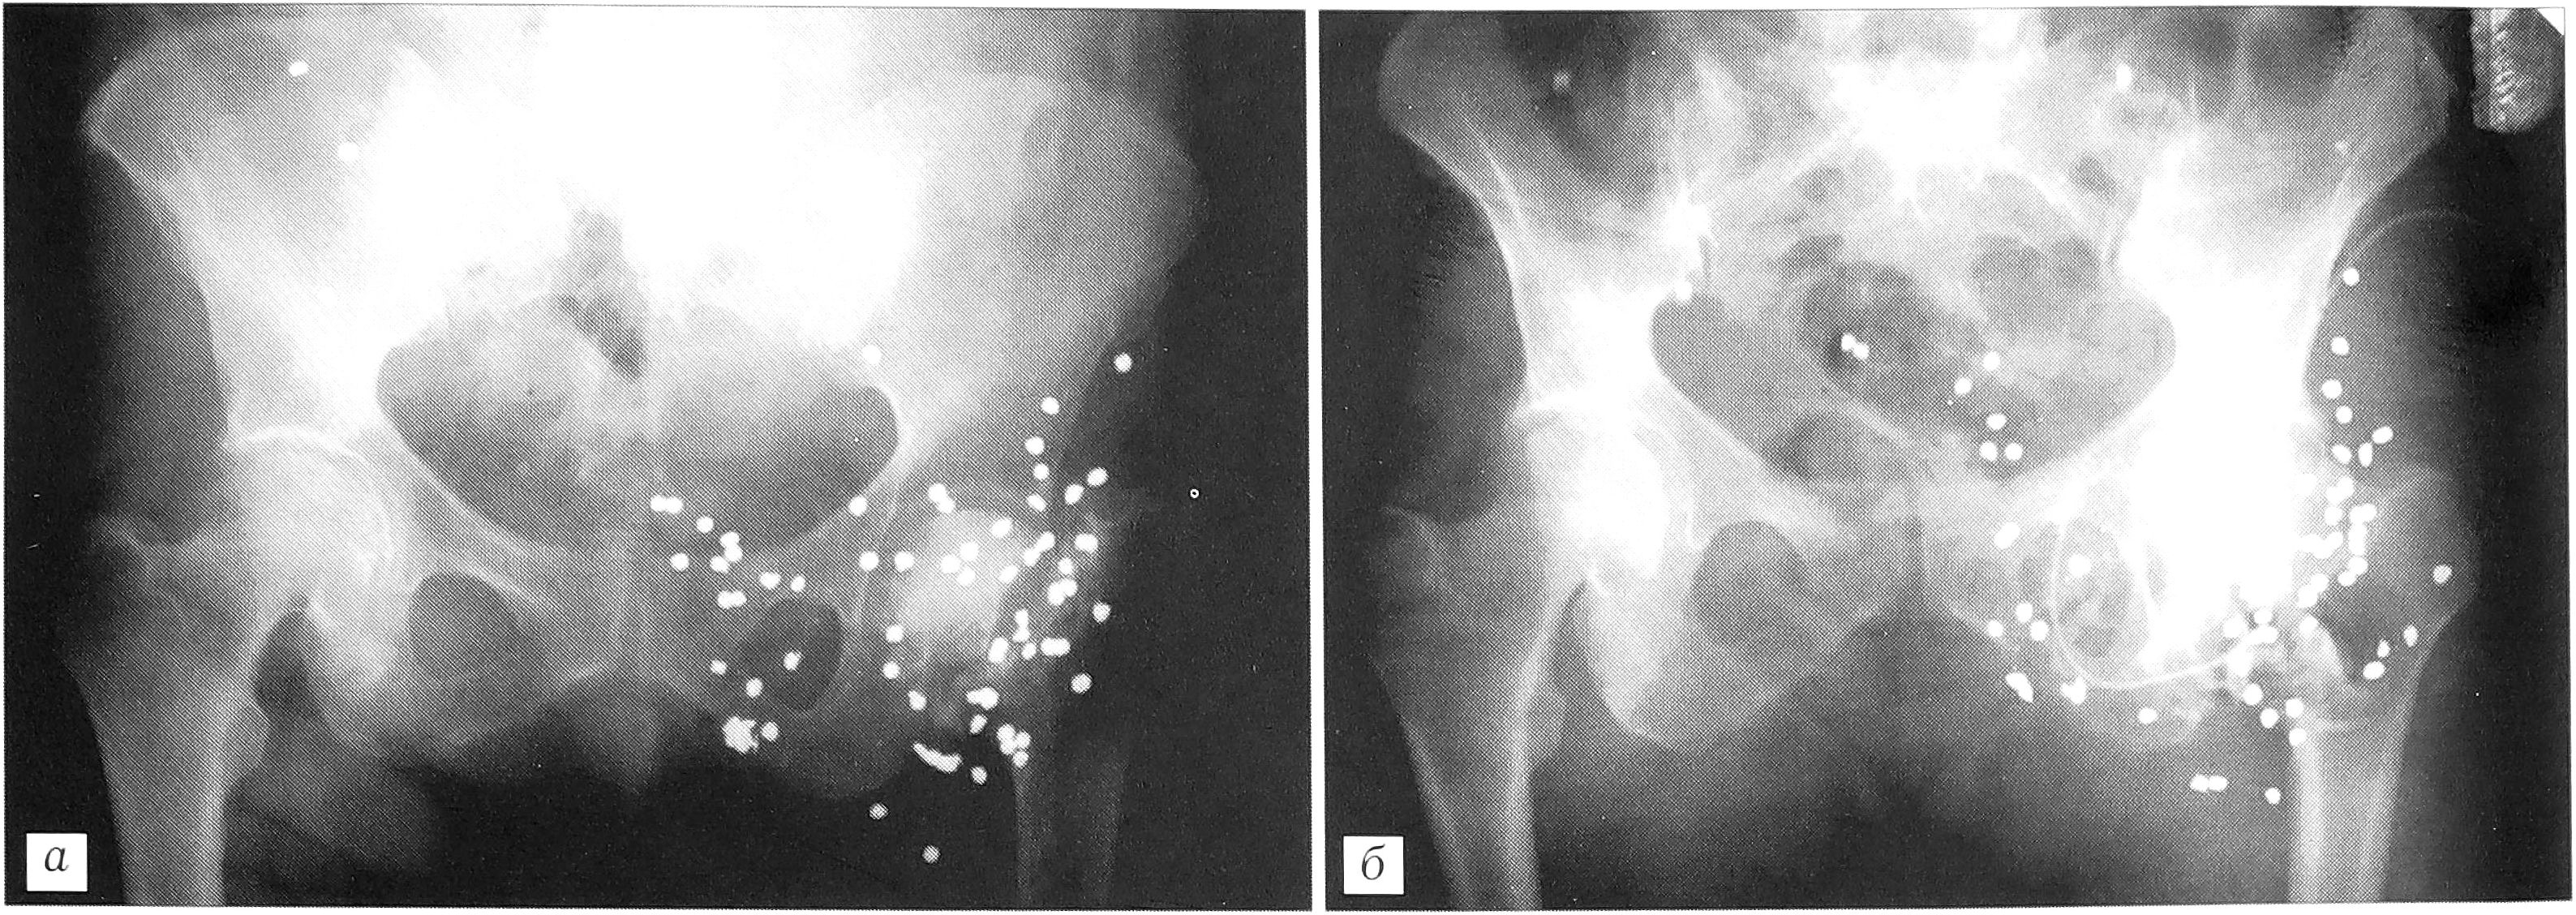

Рис. 3. Рентгенограмма (а) и фистулограмма (б) больной Б. 64 лет: остеомиелит костей, образующих левый тазобедренный сустав, после огнестрельного ранения с переломом шейки бедра.